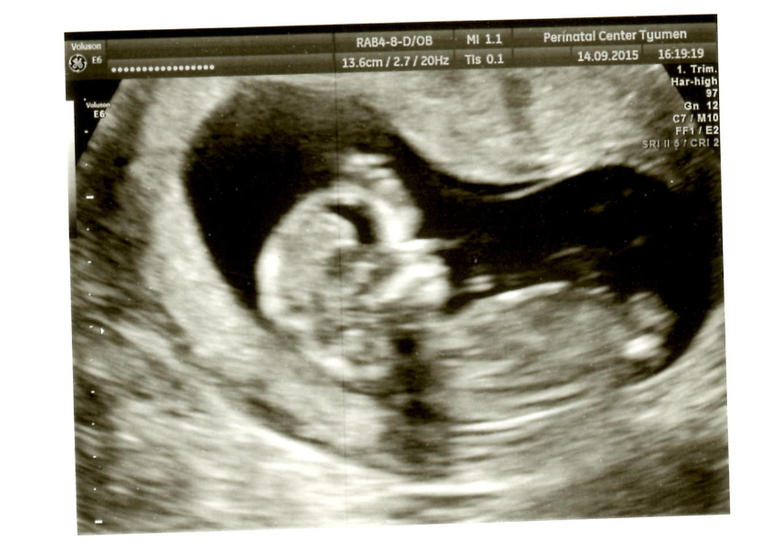

Вот и состоялась снова наша встреча с малышом)) Он так подрос за эти 2 недели.. срок еще на один день уменьшился.. должен был быть 12,6, а оказалось 12,5. Так бы и любовалась малышом хоть раз в неделю.. эх.. с малышом все хорошо.. 161 удар сердечка..он вообще похоже спал когда его смотрели.. потом когда пришел папа и нам сказали пол ребенка.. меня эмоции переполняли и он проснулся.. и мы увидели как он потягивается.. ооо.. это так мило =)) Сказали будет мальчик))) Значит внутри меня растет Савелька =)) забавно что когда я узнала о беременности сказала, что там мальчик.. так как никак не получалось зачать.. а когда мы наконец купили машину.. он зародился во мне.. Теперь папа начал мечтать какое царство игрушек у нас будет)) Я тоже рада.. всегда первым хотела мальчика.. старшим хочется брата, а младшенькой сестренку) А вот наши первые фото.. правда не такие они четкие как мне думалось будут..